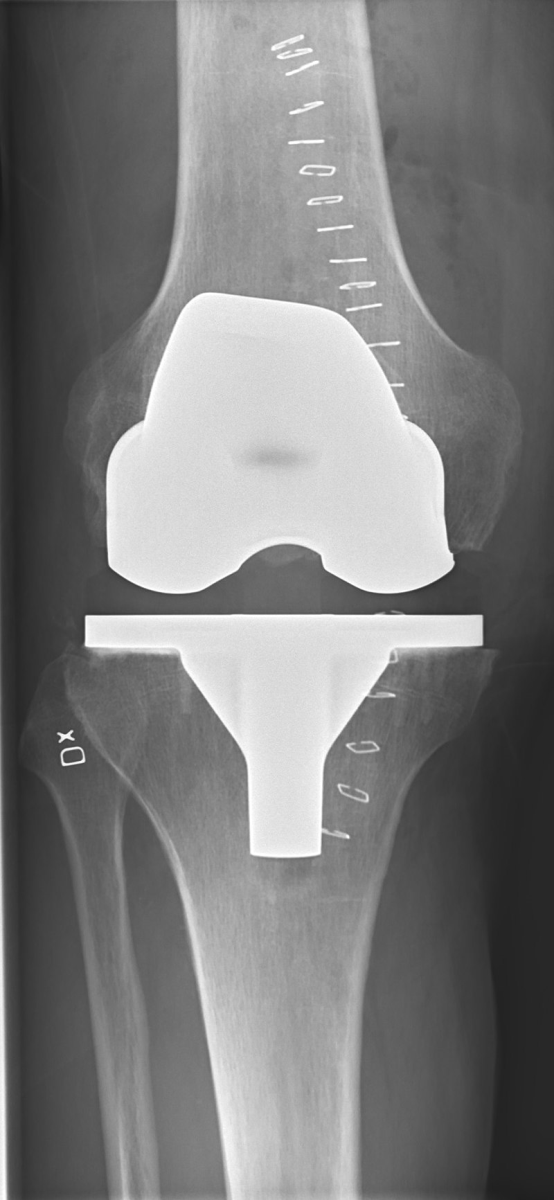

Diz protezi ameliyatında bölgesel ya da genel anestezi kullanılır. Bölgesel anestezide hasta uyanıktır ve belden aşağısını ameliyat boyunca hissetmez. Genel anestezide ise hastanın bilinci tamamen kapalıdır. Cerrahi işlem genellikle 1 ila 1,5 saat kadar sürer. Ameliyatta hasarlı kıkırdak ve kemik çıkarılır ve ardından yeni metal ve plastik implantlar dizin hizasını ve işlevini eski haline getirecek şekilde yerleştirilir.

Diz protezi yapılmış hastanın iki yönlü grafisi